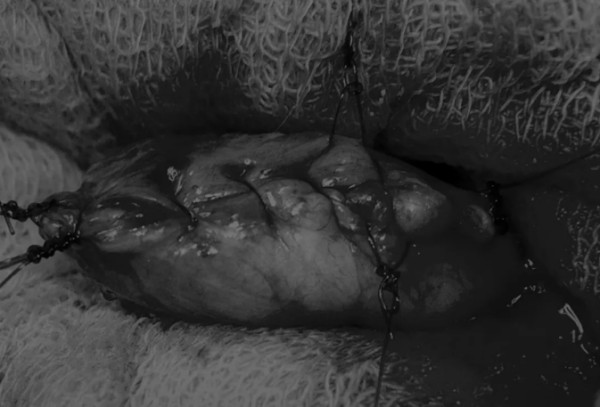

图1 将膀胱从腹腔中取出,用无菌外科敷料隔离。为了防止膀胱滑入腹部,可在膀胱顶部放置一根固定缝线,由助手通过止血钳夹住固定缝线做持续牵引

在中线开腹手术后,确定膀胱,将其取出并隔离(图1)。为了使膀胱持续暴露,可在膀胱中线两侧各放置一根固定缝线(图2)。